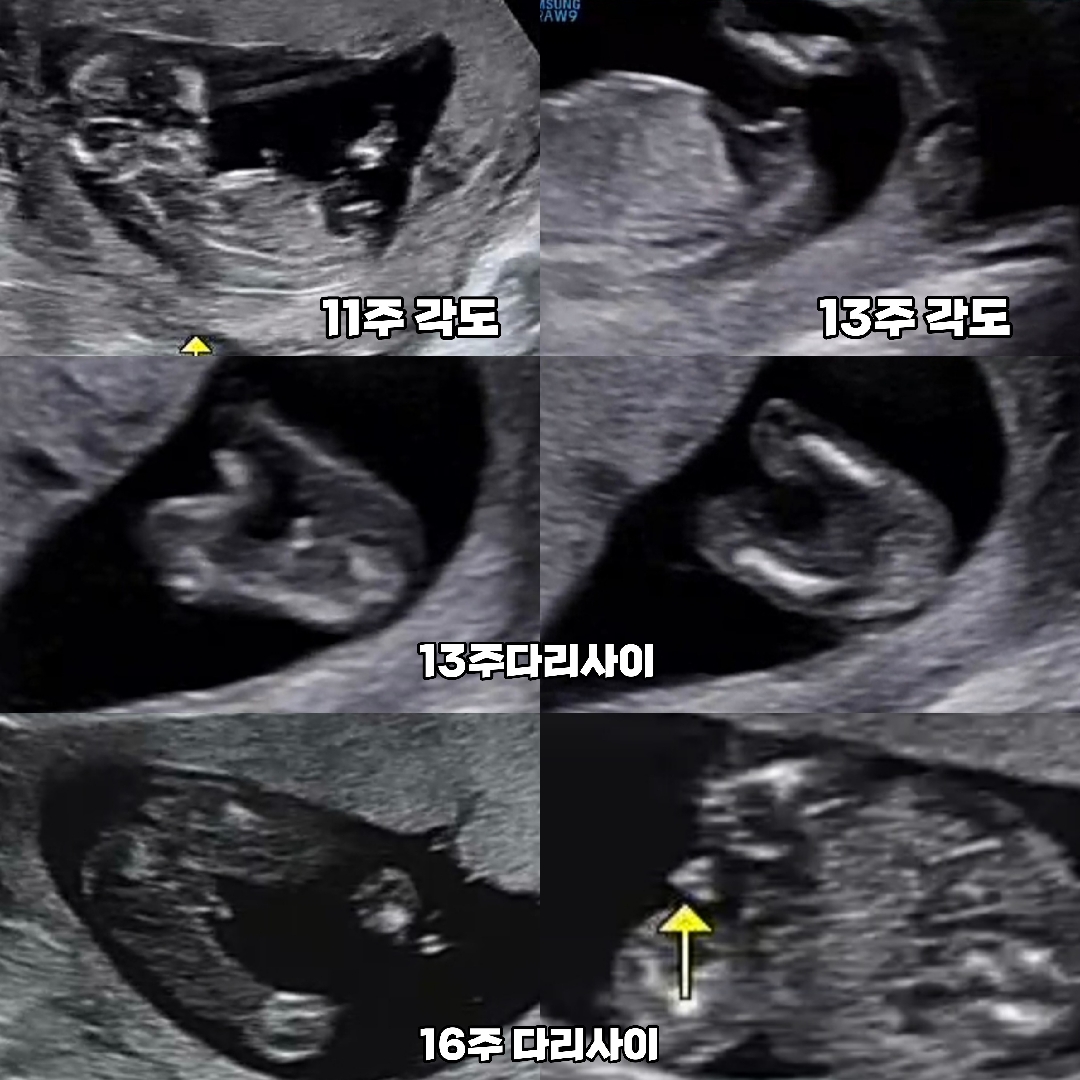

저도 아들이요오!🌶

16주 아들맘 확정 받았어용 🚀🌶💙

각도법으로 유명한 장꾸맘님께서 12주차에 아들한표 주셨었는데 13주 15주 병원에서 딸일거같다 이야기하셔서 딸로 주변에 다알렸거든요 ㅎㅎㅎ 16주 정기검진 로켓과 삼각점 발견 후 아들 확정 받았습니당 !!!! 다들 성별 확정 받으셨나요? ㅎㅎㅎ